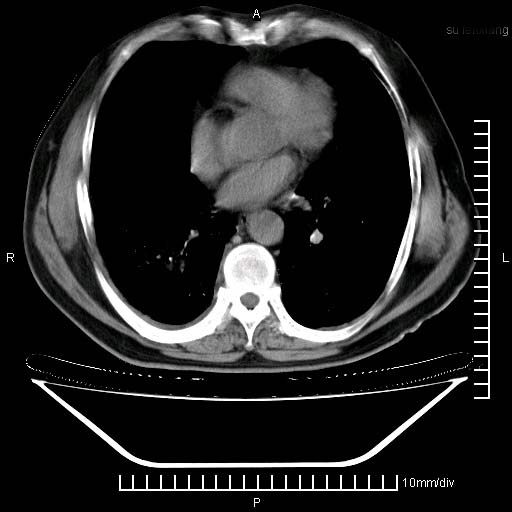

标题: CT24043:胸部增强:男性,60岁

既往肺结核,近10几天,咳嗽,咳痰,右侧胸痛,疼痛较明显,右上肺斑块考虑结核灶胸膜粘连,增强,可惜动脉期没有定好,未见强化,可延迟4分后又见较明显强化,中心见低密度影,如果说结核是边缘强化,可这个灶强化的面积挺大的,让人很挠头。

1)两肺继发性肺结核。2)右侧胸膜增厚+少量胸腔积液。